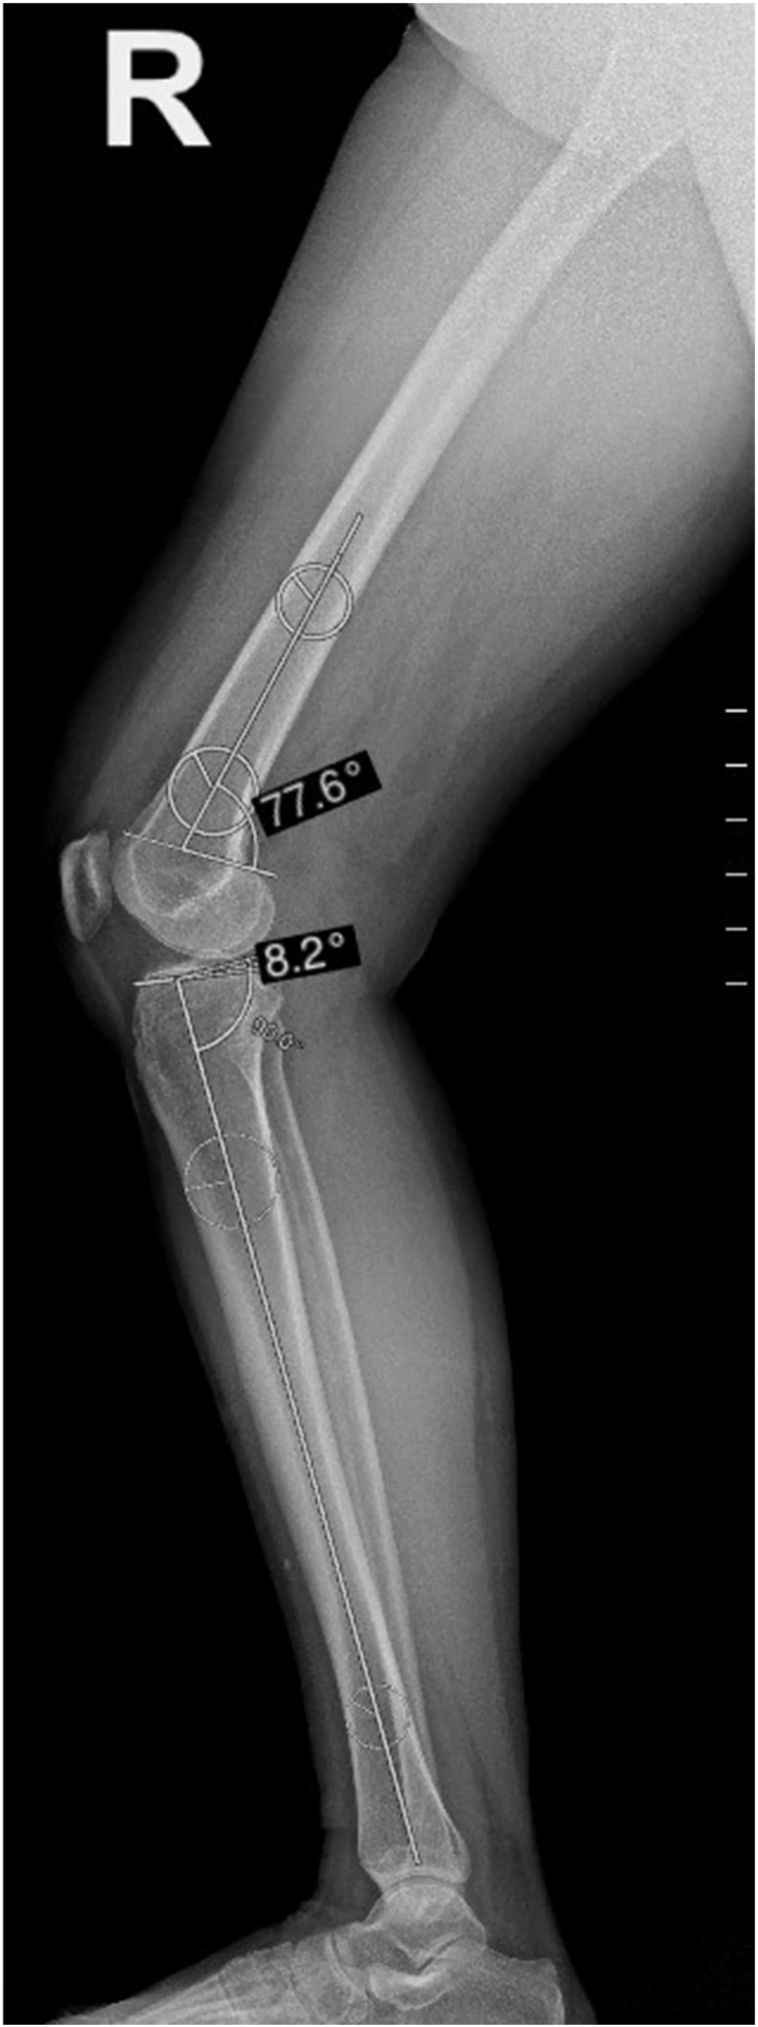

Figure 4.

Measurements of anatomical posterior distal femoral angle and PTS.

In the femur, the lateral long axis is represented by the lateral distal femur anatomical axis (DFAA). Anatomical posterior distal femoral angle (aPDFA) is formed between the DFAA and lateral distal femoral joint orientation line. The DFAA is drawn by connecting the centers of two circles. The proximal circle is positioned just distal to the junction between the middle and distal thirds of the diaphysis, while the distal circle is drawn at the distal metadiaphyseal junction. Both circles are drawn so that they are simultaneously tangent to the anterior and posterior cortices. The lateral distal femoral joint orientation line is drawn connecting the points where the femoral condyles join the anterior and posterior distal femoral metaphysis on a lateral view radiograph of the knee (Fig. 3). The normal range for aPDFA is 79°–87°.